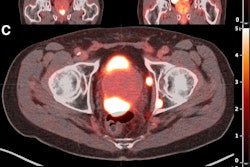

From left to right, maximum-intensity projections of screening Ga-68 PSMA-11 PET/CT, 4-h Lu-177 PSMA-SPECT/CT, and 24-h Lu-177 PSMA-SPECT/CT (top row) and corresponding quantitative maximum-intensity projections (bottom row) of 63-y-old man with mCRPC to regional and distant lymph nodes and widespread osseous metastases showing identical disease distribution on all studies both visually and quantitatively.Image courtesy of the Journal of Nuclear Medicine.

Based on visual analysis, the distribution of disease was unchanged among the three imaging methods, the researchers reported. Mean differences and agreement between four-hour and 24-hour SPECT/CT quantitative parameters were within acceptable bounds for lesion number, maximum standard uptake value (SUVmax), and SUVmean, they noted.